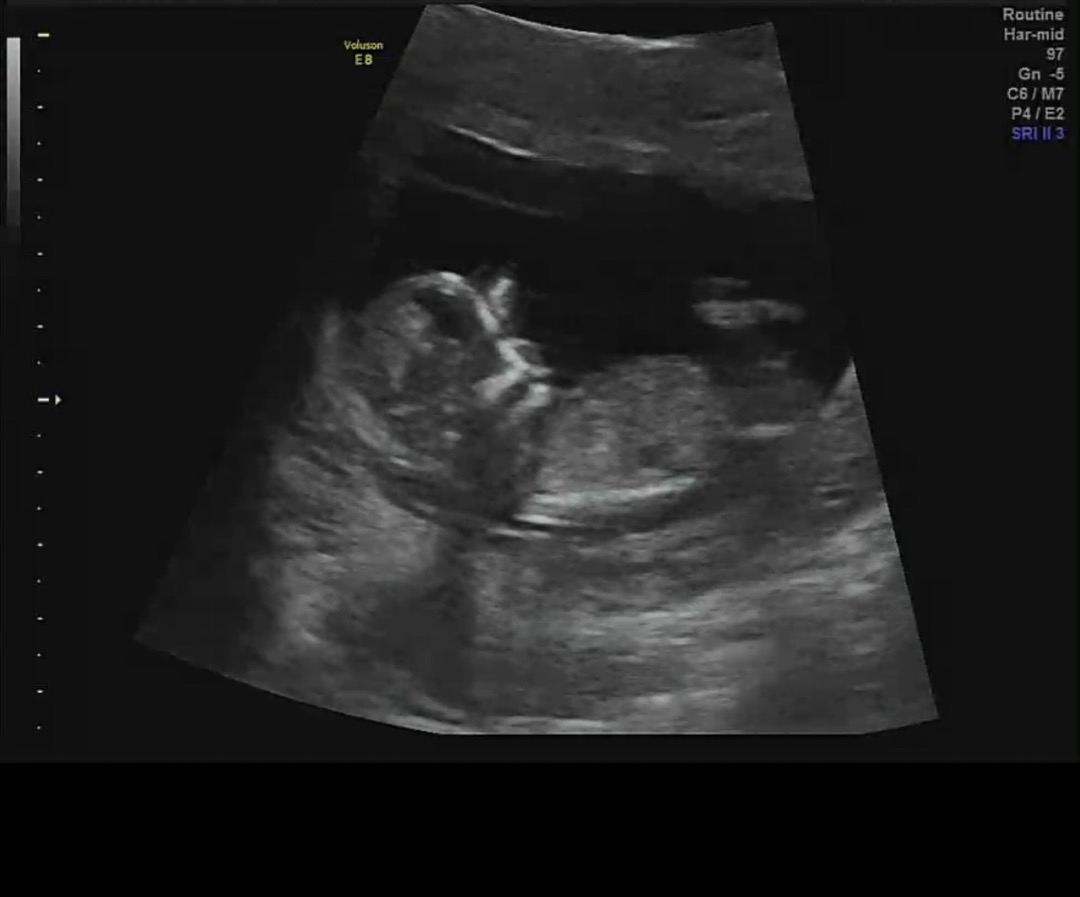

12주차 성별!!

어제 초음파보고 왔는데 딸일까요 아들일까용?! 넘 궁금해요ㅠㅠㅠ각도법 고수님들 도와주세요💗